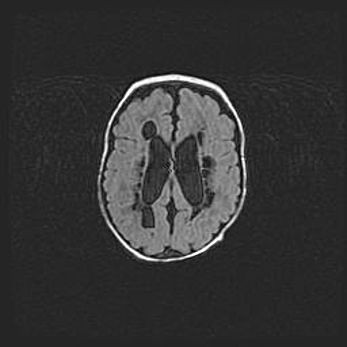

Лейкомаляция с кистозно-глиозной дегенерацией головного мозга.

Возраст: 2 месяца 25 дней

Вес: 6400 г

Окружность головы: 40 см

Срок гестации: 41 неделя

Лейкомаляцию относят к ишемически-гипоксическим повреждениям головного мозга, диагностируемым у новорожденных. При лейкомаляции в головном мозге обнаруживают очаги некроза, возникшие после тяжелой гипоксии и нарушения кровотока. В процессе морфогенеза очаги проходят три стадии: 1) развития некроза, 2) резорбции и 3) формирования глиозного рубца или кисты. Перивентрикулярная лейкомаляция (ПЛ) встречается примерно в 12% случаев среди новорожденных, обычно – у недоношенных детей, причем, частота ее зависит от массы, с которой младенец появился на свет. Наибольшее число малышей страдает лейкомаляцией, если масса при рождении 1500-2500 г.